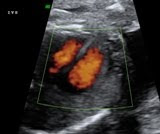

Suddenly my head is filled of Justin Bieber song-Baby. Why? because of this pic of a cute little fetus. This fetus is just 12 weeks. Actually the patient came for NT screening but she ask me if it possible for me to take a 3D pic for her. I rarely do this since the fetus is still small but, since she ask for it, I snap only one pic for her album. Here it is....

I know, the fetus is turning away from me. He/she might think that I'm bothering him/her with the sound waves and whatsoever (sorry~) or he/she is too shy to greet me (sweet~)